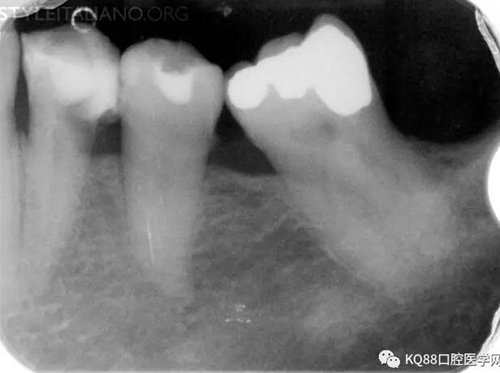

Img. 2 - Retreatment of distal canal was performed using ProTaper retreatment files. Working length was assessed electronically. Canal was shaped with a Reciproc R40, thoroughly irrigated with US activation, filled with corresponding Guttafusion obturator. Pain disappeared completely some days after retreatment. In all likelihood, incomplete preparation allowed residual pulp tissue to remain in the root canal, acting as an irritant.